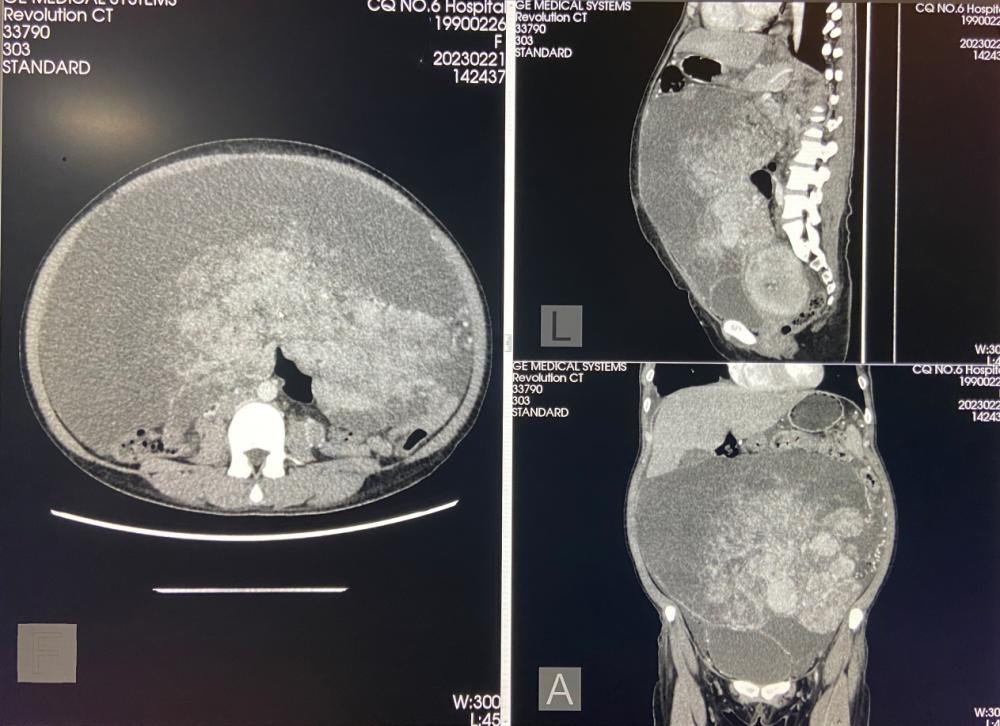

“拆弹”成功!重庆医药高等专科学校附属第一医院妇产科联合多学科成功切除巨大腹部肿瘤